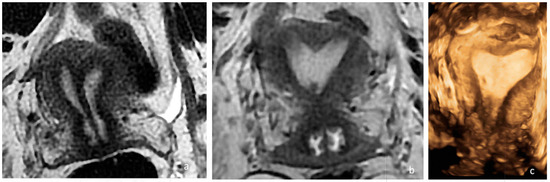

A single uterine cavity was obtained, as confirmed by MRI (Figure 2).

Figure 2. Preoperative and postoperative examination of case 1. (a) MRI T2, WI, confirmed the presence of a Müllerian anomaly and identified it as a complete septate uterus, duplicated cervix, and longitudinal vaginal septum (Class U2bC2V1 of the ESHRE/ESGE classification). Additionally, it provided information regarding the septum’s thickness, which measured 4–6 mm. (b) Postoperative MRI showing a uterine cavity. (c) Control hysterosalpingography performed 3 months after surgery, demonstrating a single uterine cavity.

The patient was discharged on the same day with a two-month estrogen pill regimen to prevent intrauterine adhesion formation. She reported no dyspareunia after the intervention.

The hysterosalpingography performed five months after surgery confirmed the presence of a single uterine cavity with an indentation of 10 mm at the fundus and a residual fundal thickness of 18 mm (Figure 2c). No intrauterine adhesions were found.